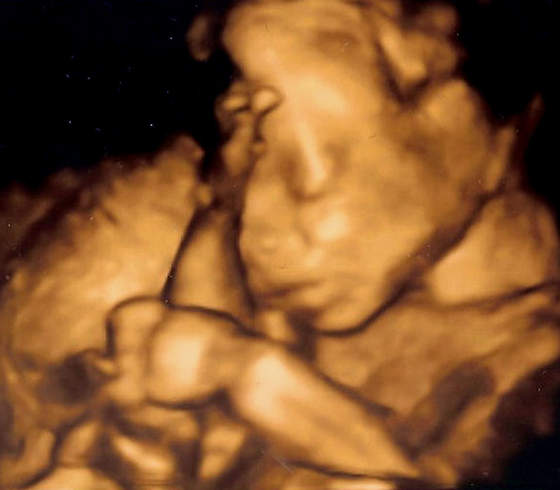

A mam jeszcze pytanie jak to jest z tym USG połówkowym, bo dziś się umawiałam i gin. stwierdził, że najlepiej w 23tc i na ten tydzień mnie zapisał. A mówiłyście, że do 22tc najlepiej?